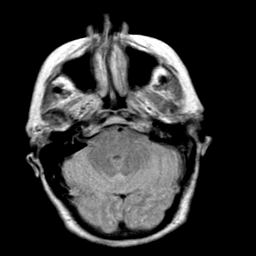

Creutzfeld-Jakob disease: proton density-weighted MR -- Slice #5

[Home][Help][Clinical] Slice 5